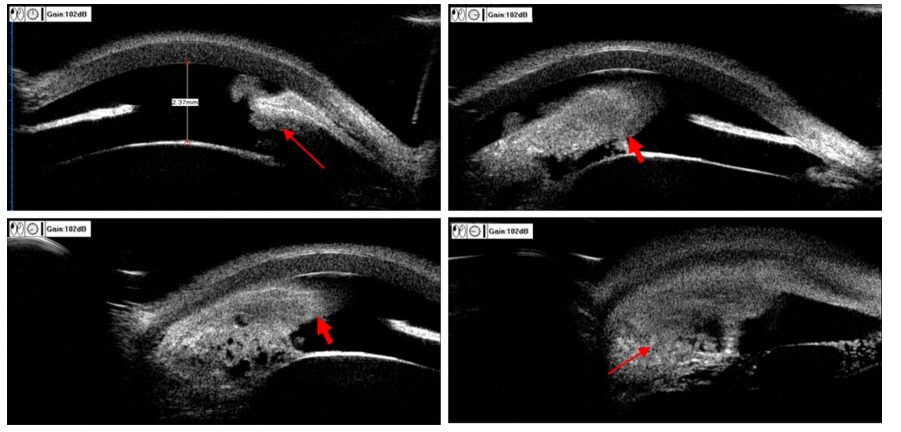

20230601151359_4350.png

图2 术前UBM图像

Figure 2 Preoperative UBM image

颞侧及下方晶状体与虹膜间(长箭头)及瞳孔区(短箭头)可见团状非均质反射声像。

Massive heterogeneous reflections were seen between the temporal and inferior lens (long arrows) and iris and pupillary area (short arrows).